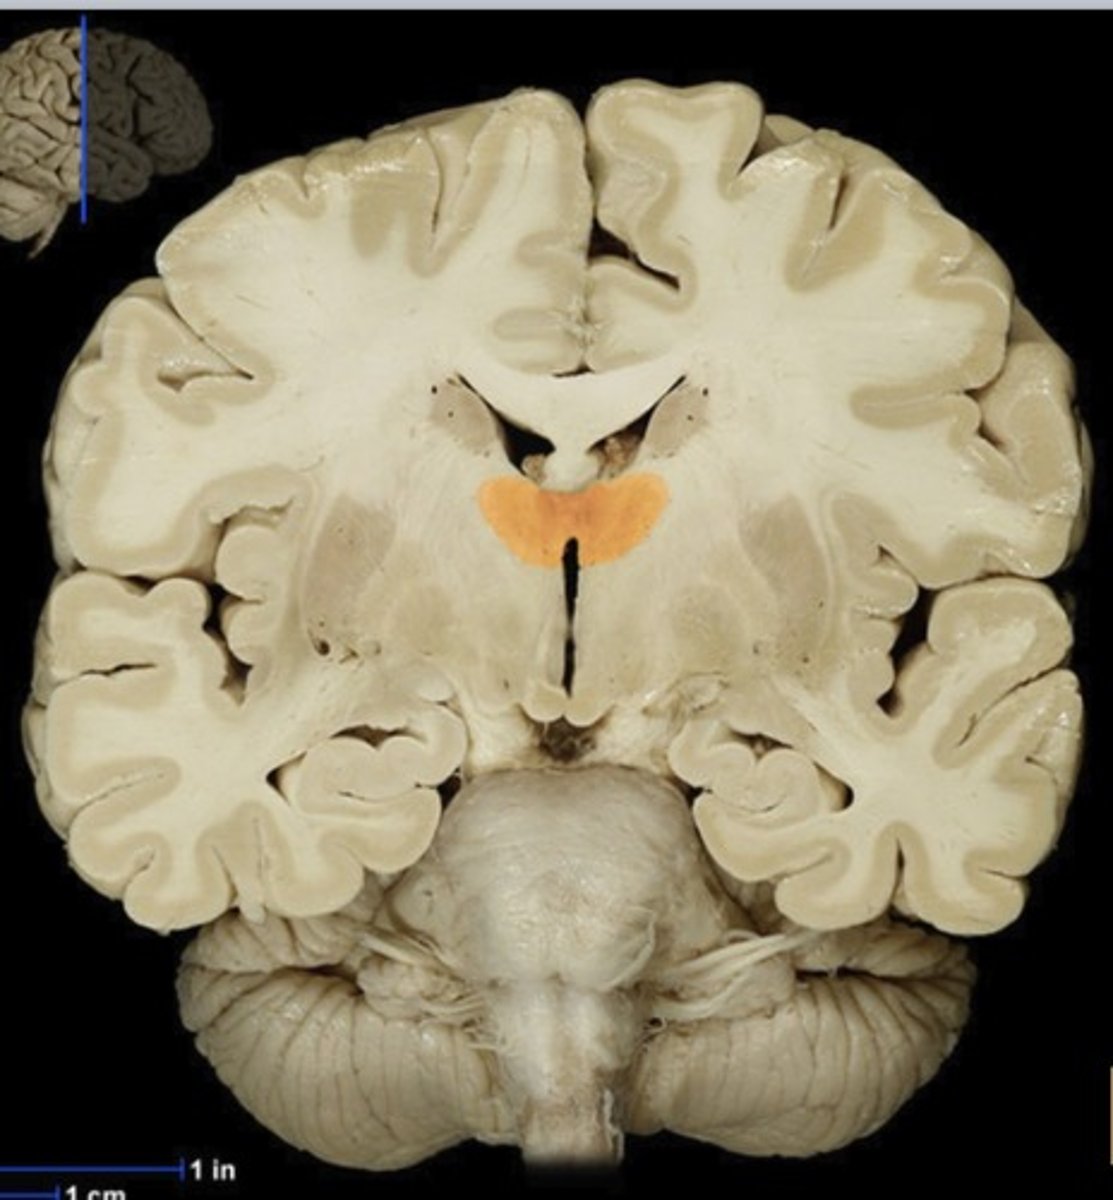

Caudate Nucleus

Name this structure

Gray matter (anterior view of coronal section)

Name this structure

White matter (anterior view of coronal section)

Name this structure

Corpus callosum

Name this structure

Fornix

Name this structure

Globus Pallidus

Name this structure

Hippocampus

Name this structure

Hypothalamus (anterior view of coronal section)

Name this structure

Lateral Ventricles

Name this structure

Mamillary body

Name this structure

Putamen

Name this structure

Thalamus (anterior view of coronal section)

Name this structure

Third Ventricle (anterior view of coronal section)

Name this structure